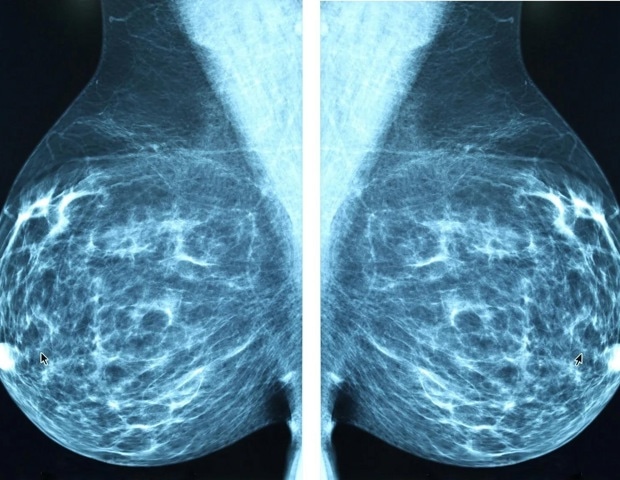

Каждой женщине старше 40 лет рекомендуется пройти маммографию для раннего выявления рака молочной железы. Но результаты могут быть неубедительными для женщин с плотной тканью молочной железы. Этих женщин часто отправляют на УЗИ — технологию, которая также не работает с плотной тканью молочной железы.

Ультразвук работает, посылая звуковые волны через датчик в грудь. Звук отражается от таких структур, как массы, и записывается. Когда все работает идеально, звук передается напрямую от массы обратно к зонду. Но при плотной грудной выдаче звук рассеивается, не дойдя до массы, вызывая «акустический захламление» изображения. Доброкачественная заполненная жидкостью киста, которая на изображениях должна выглядеть черной, внутри часто выглядит серой, как и раковая опухоль.

Новый метод ничего не меняет в производстве ультразвука, но улучшает способ обработки сигналов. Обычный ультразвук полагается на амплитуду сигналов, превращая высокие и низкие сигналы в черные, белые или серые. Новый метод «основан на когерентности», то есть изображение зависит от того, насколько сигналы похожи на соседние сигналы.